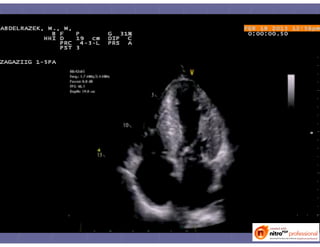

2D2D ––viewsviews